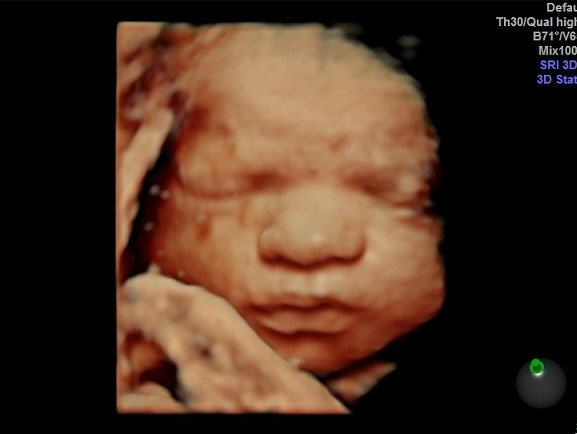

Gallery